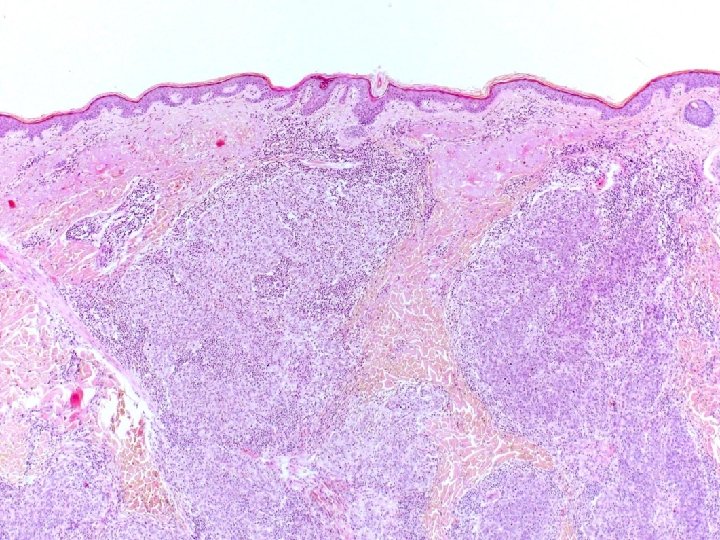

�Case number: 189 �Female aged 48 years. �A. L. L. Had bone marrow transplant.

�Case number: 189 �Female aged 48 years. �A. L. L. Had bone marrow transplant. �Had susequent Gv. HD. �Now thickened red, swollen skin �? Leukaemic infiltrate. �Positive for CD 79 a, CD 20, CD 10, CD 34, Td. T. �Negative for CD 2, CD 3 and CD 117.

� Most popular diagnosis � B lymphoblastic lymphoma